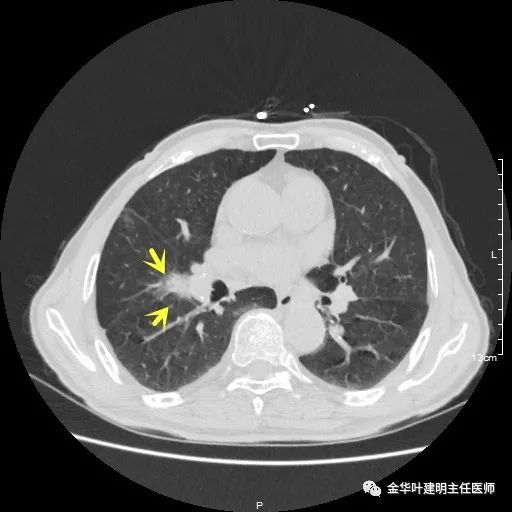

以上示右中叶病灶4。也是囊腔型病灶,病灶大,囊壁是磨玻璃密度,亦是较为典型的囊腔型肺癌影像。单病灶看,需中叶切除来治疗,因病灶3的存在,中叶切除可同时解决病灶3与病灶4。

以上示右下叶病灶5。也是主病灶,是实性块状分叶的占位性病变,基本可以肯定是肺癌。单病灶看需下叶切除并清扫淋巴结。